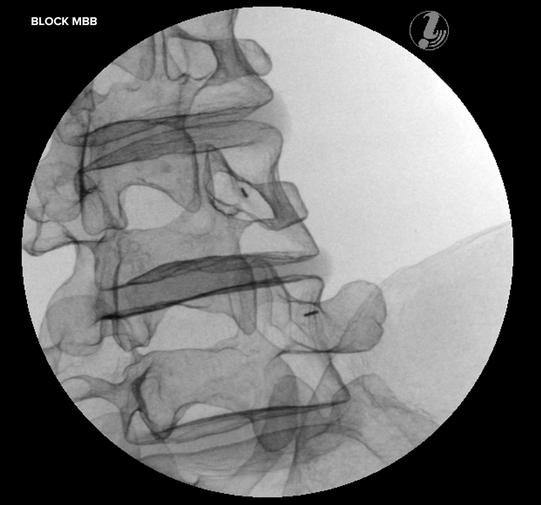

TRENAŻER DO ZNIECZULANIA ZEWNĄTRZOPONOWEGO W ODCINKU LĘDŹWIOWYM POD KONTROLĄ USG

Trenażer do znieczulania zewnątrzoponowego w odcinku lędźwiowym pod kontrolą USG umożliwia naukę diagnozowania źródła bólu, identyfikacji tkanki docelowej i narażonych struktur, przy użyciu USG i anatomicznych punktów.

Przy użyciu symulatora można przeprowadzać m.in:

• znieczulenie zewnątrzoponowe TFSI

• blokadę gałęzi podstawnej-przyśrodkowej

• blokadę stawu krzyżowo-biodrowego